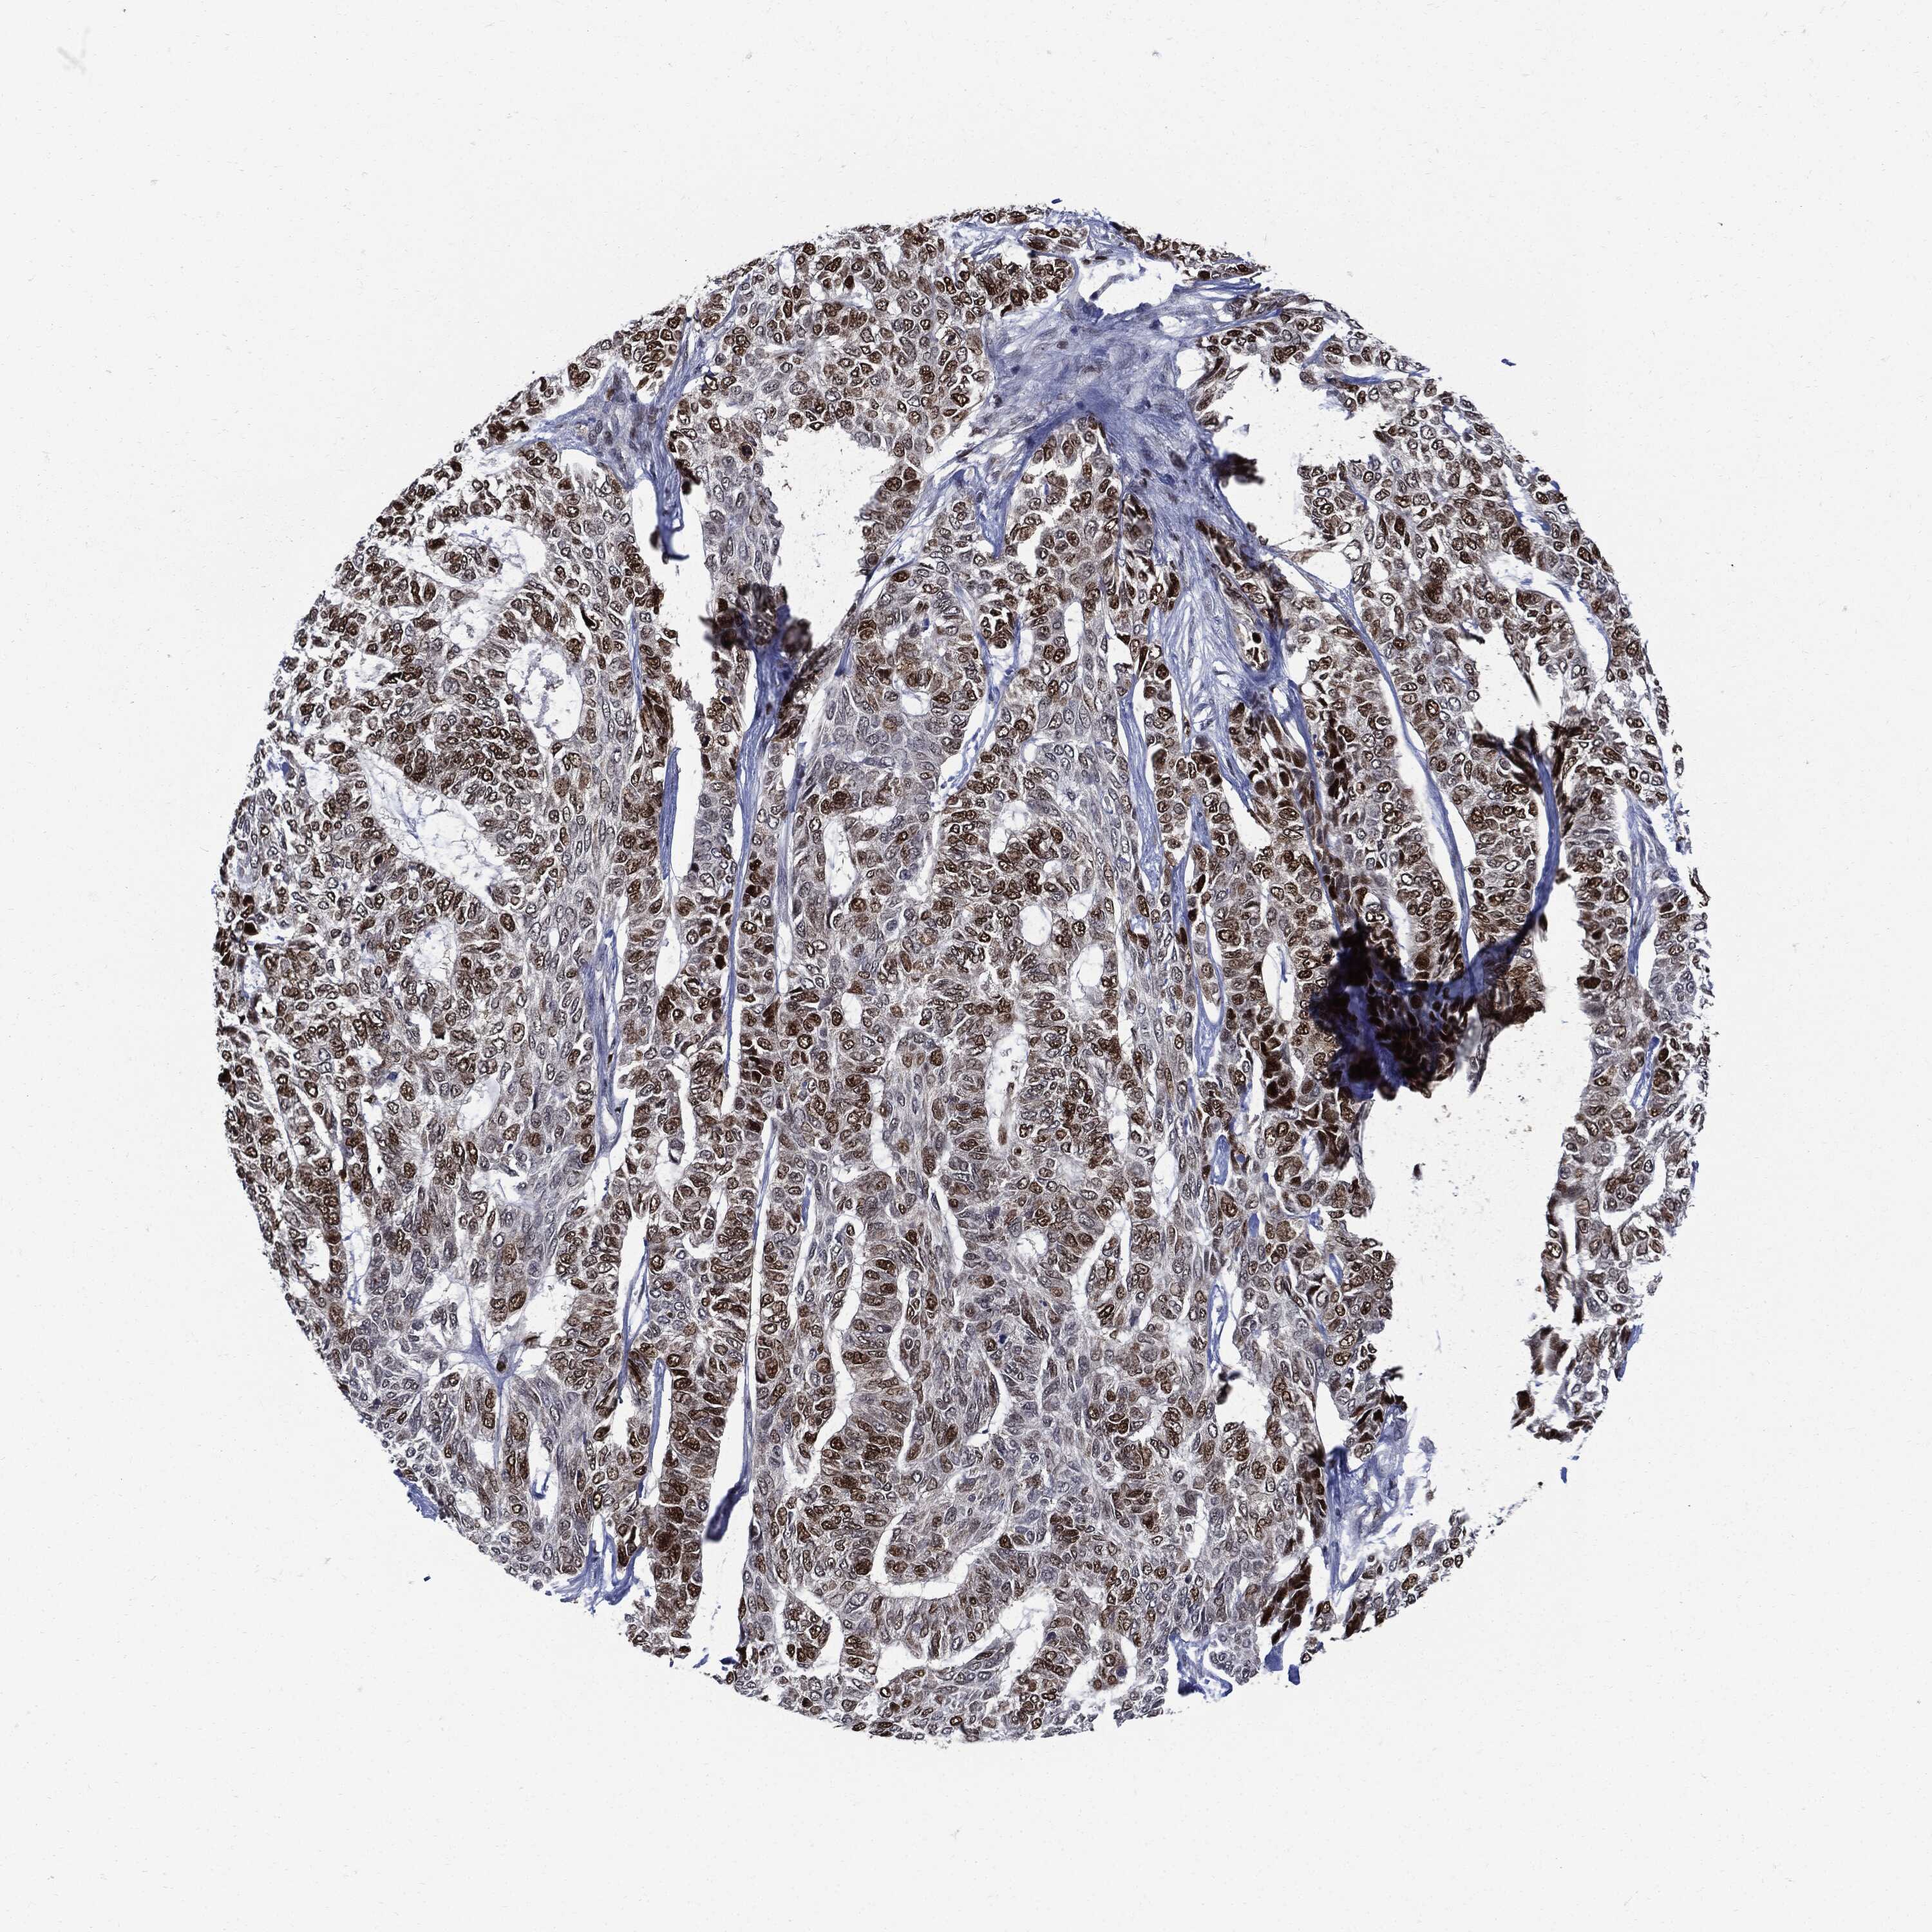

SKIN CANCER - Protein expressioni

A mouse-over function shows sample information and annotation data. Click on an image to view it in a full screen mode. Samples can be filtered based on level of antibody staining by selecting one or several of the following categories: high, medium, low and not detected. The assay and annotation is described here.

Each image is clickable and will lead to virtual microscopy that enables deeper exploration of all samples and also displays staining intensity scores, fraction scores and subcellular localization as well as patient and tissue information for each sample.

Staining

High

Medium

Low

Not detected

Intensity

Strong

Moderate

Weak

Negative

Quantity

>75%

75%-25%

<25%

None

Location

Nuclear

Cytoplasmic/membranous

Cytoplasmic/membranous,nuclear

Basal cell carcinoma

Squamous cell carcinoma, NOS

Squamous cell carcinoma, metastatic, NOS